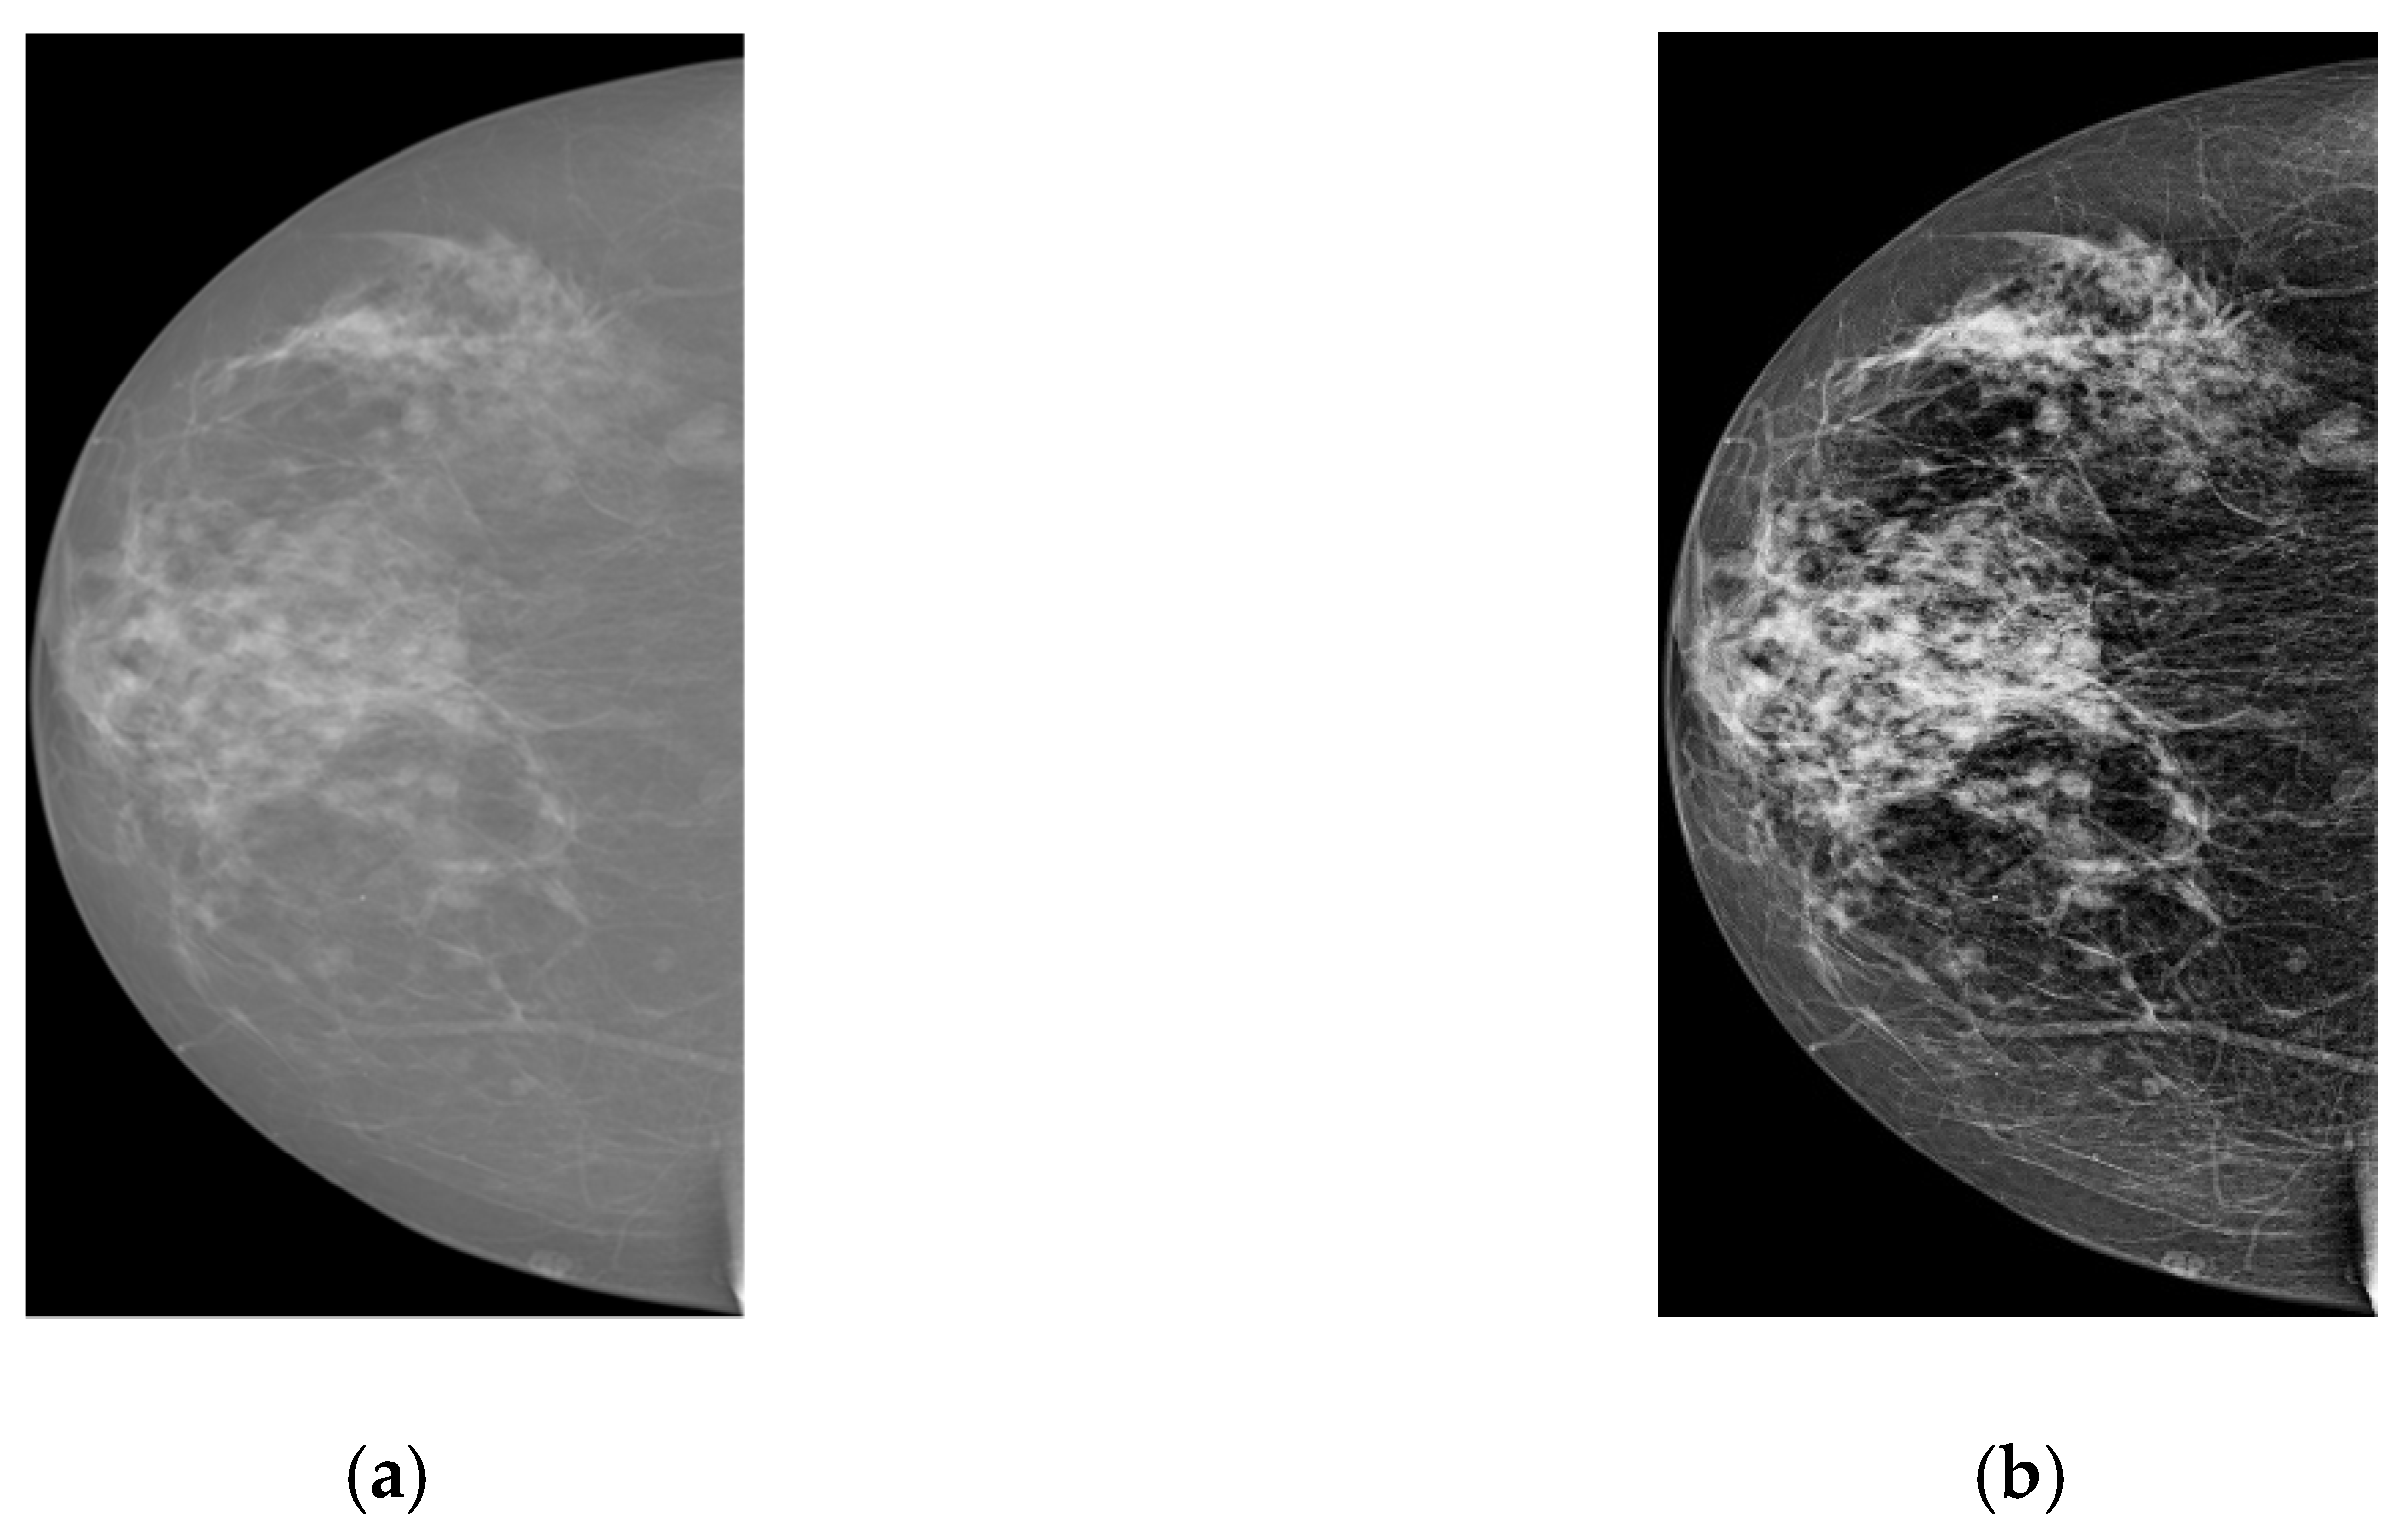

In the previous subsections, we discussed the overall flow of the proposed deep learning method from RoI generation, to improving classification accuracy of the object detection model with the help of a CNN-based classifier. All procedures are firstly performed on our private dataset as it has more and higher quality mammograms. Using the pre-trained model, we aim to fine-tune the network parameters for the INbreast database. However, before starting training on this dataset, some pre-processing procedures should be done. Firstly, two datasets contain mammograms with different intensities and contrast. Figure 4 shows two samples from each database for reference. In order to reduce the dataset difference for more accurate adoption, we enhance the texture and contrast (e.g., using CLAHE [29]) of INbreast mammograms. These pre-processing steps take place after breast region extraction but before square patch generation. Figure 5 shows samples before and after pre-processing operations. As seen from Figure 5b, the enhanced image now displays clear tissue information and is quite similar to mammograms in our private dataset.

Figure 5. Texture and contrast enhancement. (a) original image; (b) enhanced image.